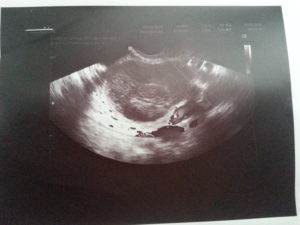

Вода, скопившаяся в позадиматочном пространстве, выявляется во время проведения ультразвукового исследования органов малого таза. Нынешнее оборудование позволяет с максимальной точностью определять её объём.

Жидкость позади матки можно обнаружить при проведении ультразвукового исследования. Чтобы уточнить природу ее происхождения, требуется провести пункцию. Ее делают во время лапароскопической операции.

Свободная жидкость в позадиматочном пространстве диагностируется с помощью УЗИ

С его помощью можно увидеть и распознать даже минимальное количество жидкости как в матке, так и позади нее. Визуально на экране ультразвукового аппарата скопление небольшого количества жидкости напоминает неширокую полоску темного цвета.

Ультразвуковое исследование является одним из самых доступных и достоверных методов, с помощью которого можно обнаружить даже небольшое содержание жидкости в полости малого таза.

На экране УЗ-сканера жидкостные образования за маткой выглядит черного или темно-серого цвета, чаще имеет форму узкой полоски, если ее количество небольшое.

При большом количестве она растекается между органами и принимает неправильную форму.

Точного количества жидкости за маткой в миллилитрах с помощью этого метода определить невозможно из-за того, что жидкость растекается между складками брюшины и органами и не принимает какой-то строгой формы. Тем не менее для описания количества жидкости на УЗИ в полости малого таза существуют определенные критерии.

Врач измеряет наибольшую длину вертикального уровня жидкости за маткой. Если высота уровня жидкости составляет до 10 мм, то ее количество считается незначительным.

Если высота уровня жидкости составляет от 10 мм до 50 мм, то количество ее считают умеренным, более 50 мм – значительным.